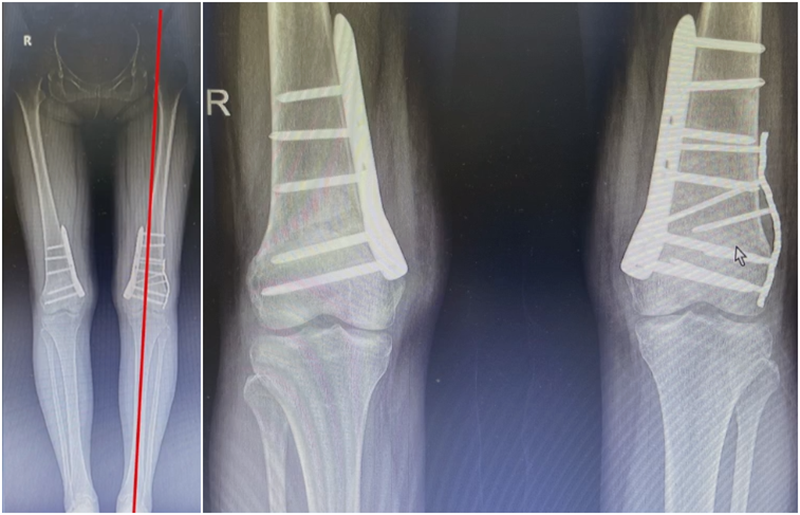

进行翻修,术前力线显示内翻。

近端螺钉松开,调整力线,重新固定后,在外侧加小钢板抗旋。

术后10周复查,力线较好。